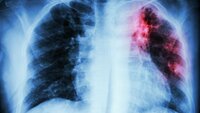

Flere pasienter slipper åpen hjertekirurgi

Antallet som får ny hjerteklaff uten åpen kirurgi, har blitt firedoblet på fem år.